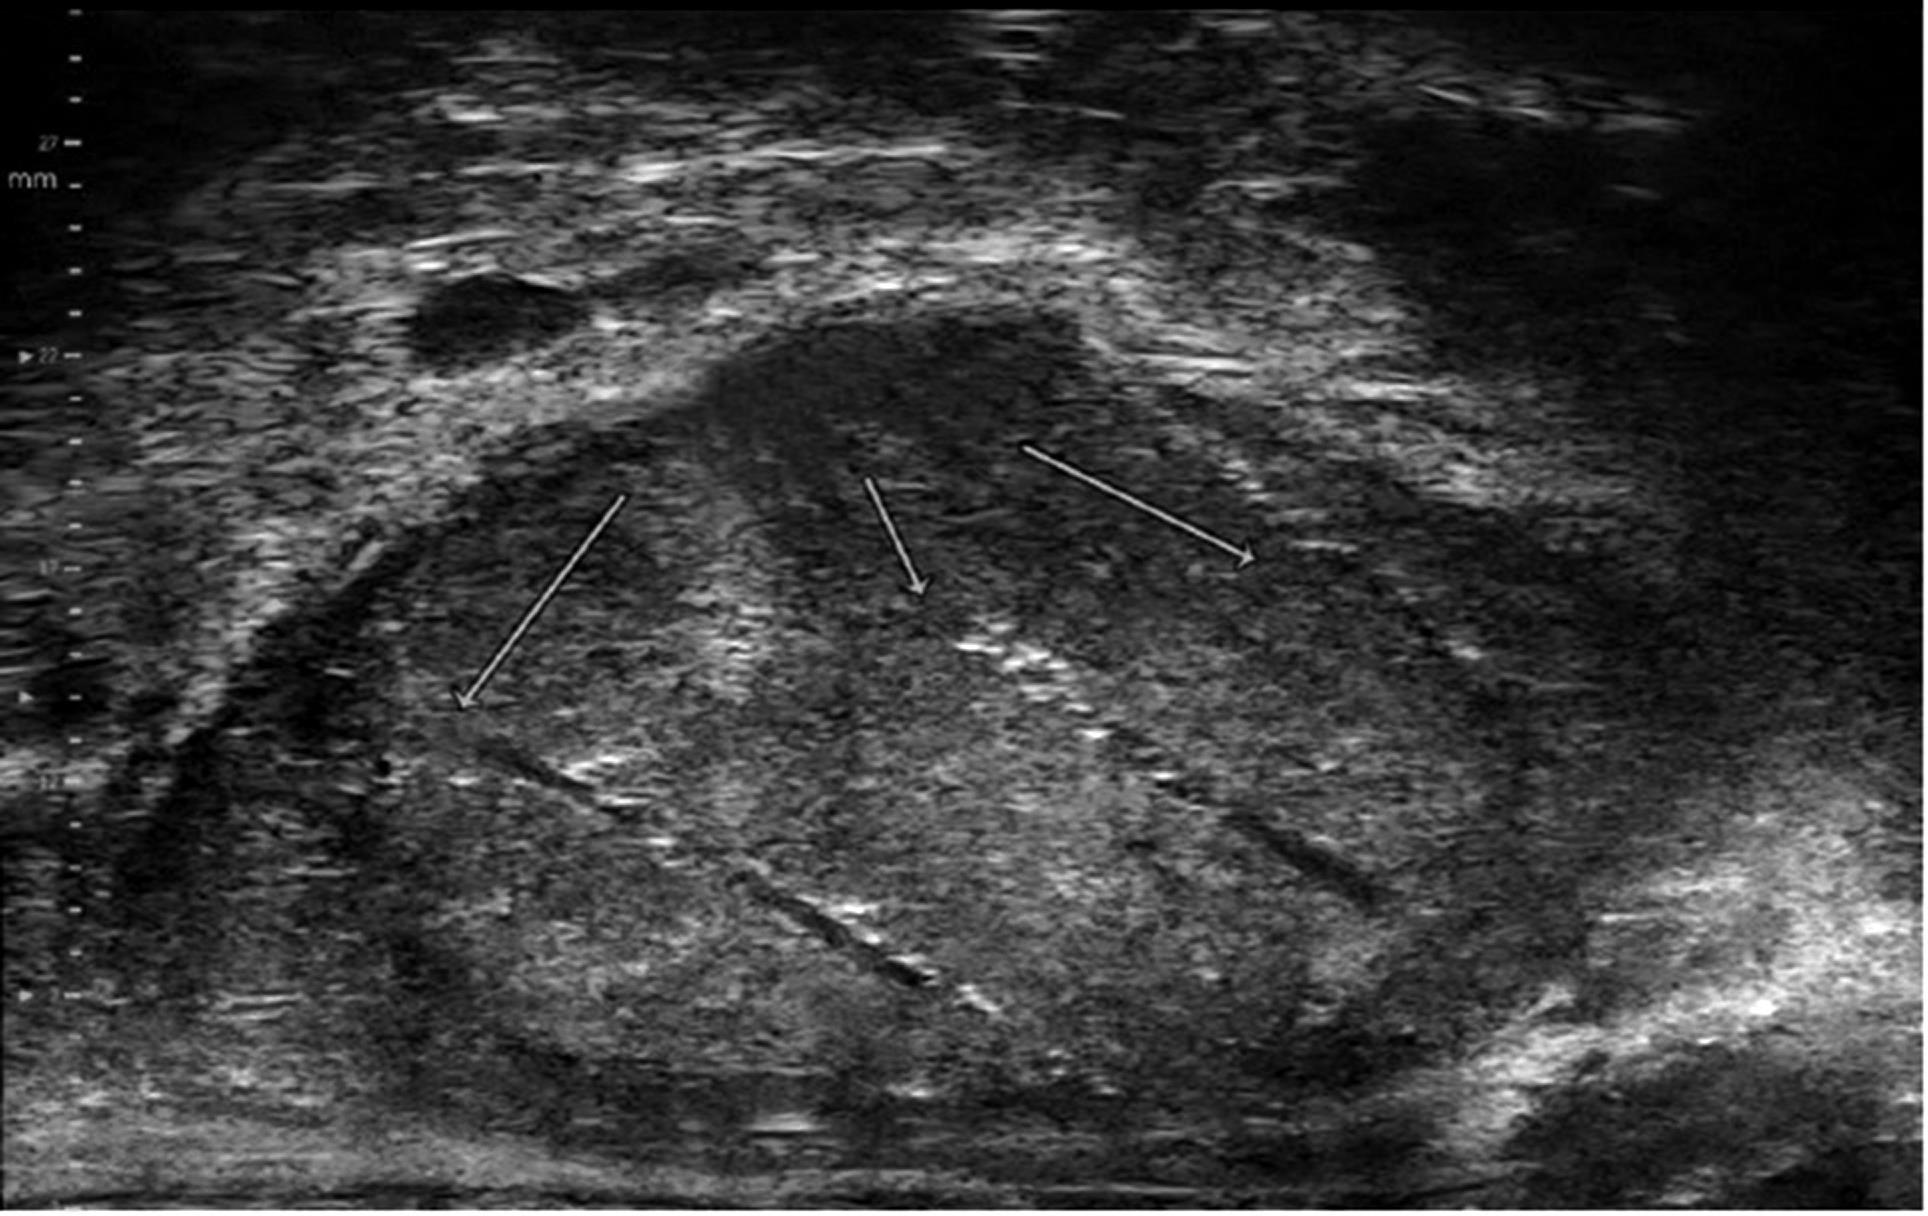

Разница между микроультразвуком и традиционными эхографическими исследованиями заключается в использовании высокочастотных звуковых волн на 29 МГц (вместо 5-10 МГц). В результате этого микроультразвук дает на 300% более точные и четкие изображения на клеточном уровне ткани. Он может обнаружить даже подозрительные участки опухолей размером с волосок.

Трансректальная и трансперинеальная целенаправленная биопсия простаты относятся к малым процедурам в урологии. Во время процедуры специальный зонд вводится в прямую кишку, чтобы визуализировать простату, обнаружить подозрительные участки опухолей и провести биопсию. Процедура занимает всего около 10 минут и проводится амбулаторно с использованием легкой анестезии на основе раствора лидокаина. Трансперинеальная биопсия (когда игла вводится через промежность) проводится в стационарных условиях с легкой анестезией, и пациент может покинуть клинику в тот же день.

Биопсия простаты под контролем микроультразвука эффективно выявляет подозрительные участки рака простаты и практически на 100% точно нацеливает забор ткани из подозрительного участка. Ее эффективность подтверждена научными исследованиями.

Однако эффективность не ограничивается этим. Возможно проведение FUSION биопсии. Этот метод представляет собой вершину достижений биопсии простаты и является новейшим достижением современной медицины. Если у пациента есть МРТ-исследование, в ходе процедуры можно объединить изображение МРТ с изображением микроультразвука в режиме «live» для самой точной диагностики и забора тканей из подозрительного участка.